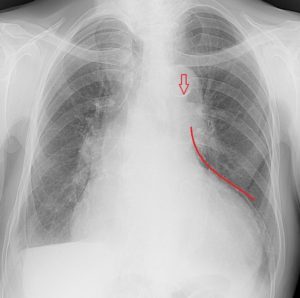

Расшифровка цифровых кодов флюорографии с примерами

01 - Кольцевидная тень (полость).

02 - Затемнение в легочной ткани (инфильтрация,ателектаз, округлая тень, среднедолевой синдром и др.).

03 - Очаговые тени в легочной ткани.

04 - Расширение тени средостения, в том числе увеличение размеров корня.

05 - Плевральные выпоты.

06 - Фиброзные изменения в легочной ткани (выраженные).

07 - Фиброзные изменения в легочной ткани (ограниченные).

08 - Повышение прозрачности легочной ткани (эмфизема локальная и распространенная).

09 - Изменения плевры (сращения, плевральные наслоения, обызвествления) выраженные.

10 - Изменения плевры (сращения, плевральные наслоения, обызвествления) ограниченные.

11 - Петрификаты крупные в легочной ткани - множественные (5 и более).

12 - Петрификаты крупные в корнях - множественные (5 и более).

13 - Петрификаты мелкие в легочной ткани - множественные (5 и более).

14 - Петрификаты мелкие в корнях - множественные (5 и более).

15 - Петрификаты крупные в легочной ткани - единичные.

16 - Петрификаты крупные в корнях - единичные.

17 - Петрификаты мелкие в легочной ткани - единичные.

18 - Петрификаты мелкие в корнях - единичные.

19 - Изменения диафрагмы, не связанные с плевральной патологией (диафрагмальная грыжа, высокое стояние диафрагмы и т. д.).

20 - Состояние после операции на легком.

21 - Изменения скелета грудной клетки (сколиоз, кифосколиоз, костная мозоль, добавочное ребро, остеофиты и т. д.).

22 - Инородное тело (проецируется на легочную ткань, тень средостения в мягких тканях).

23 - Сердечно-сосудистая патология.

24 - Прочие - добавочная доля.

25-норма.

25 - Норма.

26 - Брак.

Примечания:

При сочетании нескольких из перечисленных изменений каждое из них отмечается соответствующим кодом в каждой графоклетке.

Локализация, протяженность изменений отмечается дробью по второй графоклетке 1; 2; 3; 4; в числителе - правое легкое, в знаменателе - левое легкое (по полям).

Номер шифра легочных полей: 1 - первое, 2 - второе, 3 - третье, 4 - первое и второе, 5 - первое и третье, 6 - второе и третье, 7 - первое, второе и третье.

В третьей графоклетке вместо подписи врача подставляют личный номер рентгенолога.

Вызов на контрольное рентгеновское дообследование отмечается в четвертой графоклетке цифрой 1.